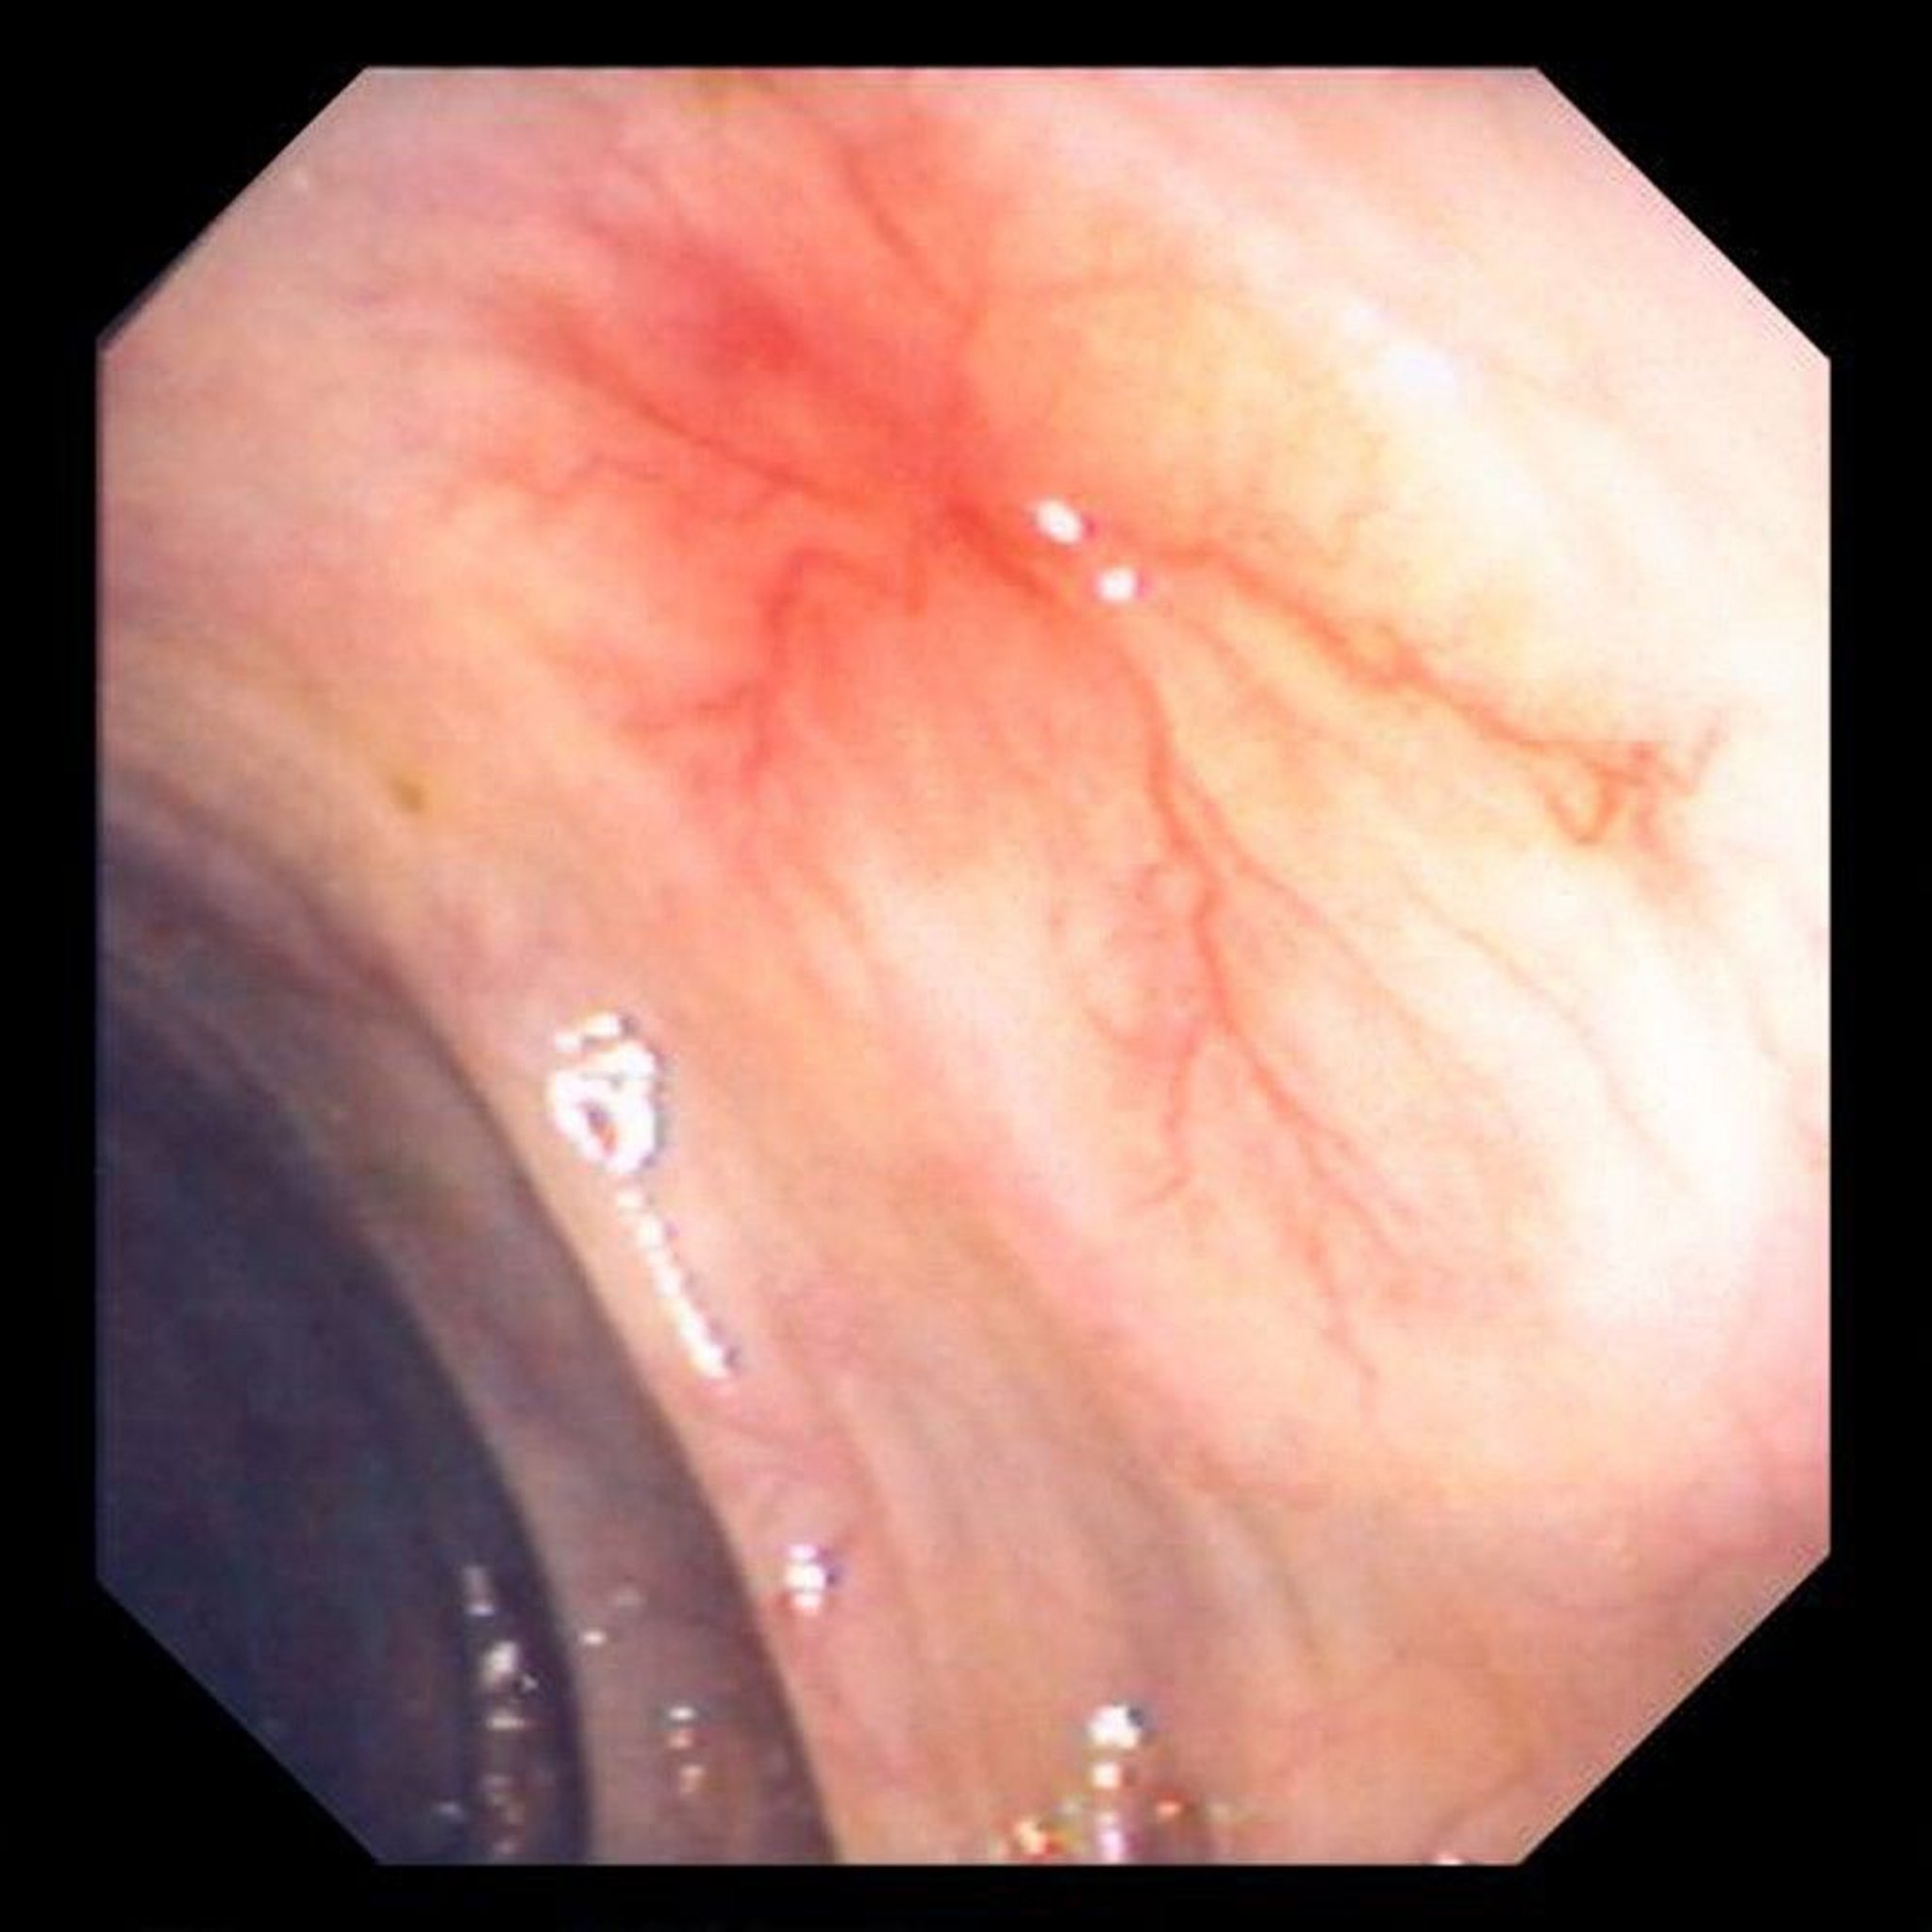

Angiodysplasia

This photo shows vascular ectasia in the bowel wall.

Image provided by David M. Martin, MD.